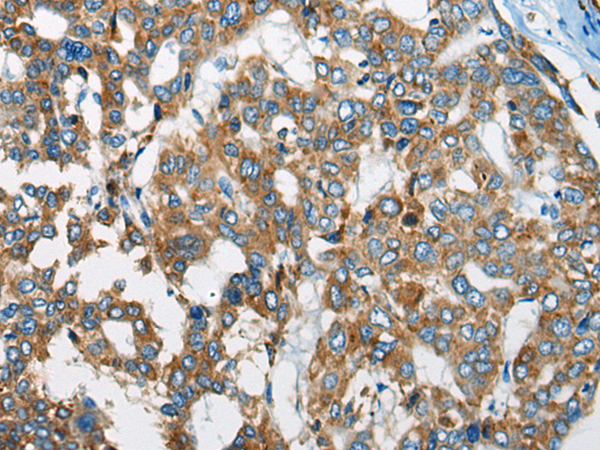

ELISA, IHC |

IHC positive control: |

Human liver cancer and human prostate cancer |

IHC Recommend dilution: |

20-100 |